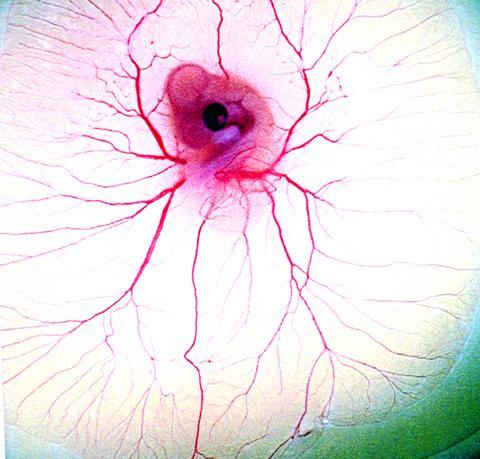

A photograph of a five-day old chicken embryo, titled Spider's Web, looks like a bloodshot eyeball, with veins spreading out from a dark center over a white yoke. Harmony, a picture of the 3D structure of an HLA molecule cannot but amaze, looking as it does like some sort of electronic scrawl, possibly created out of neon. While the explanations accompanying the pictures are strictly scientific both in content and in tone, this does no prevent the non-scientific imagination taking off on wondrous flights of fancy. A photo of the "structural detail of a human kidney" is titled Gorgon, which might send the mind in a particular direction, but on the whole these concessions to the imaginative restrict rather than expand the horizons that these pictures open up.

PHOTO COURTESY OF ESLITE